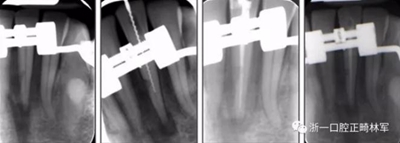

由于下頜中切牙間沒有間隙行下頜正中切開術,故進行術前正畸擴展間隙。下頜前牙粘托槽,中切牙托槽成交放置,將中切牙牙根分開。使用0.018X0.018鎳鈦絲及置于下頜左、右中切牙之間的推簧推間隙。3個月后拍攝CBCT示已有足夠間隙行下頜正中截骨術。

術后第9天開始旋轉擴弓器,每天轉2次,每次轉90度,即擴開0.5mm。每隔1周進行檢查,目標上頜擴開9mm,下頜擴開6mm。18天后,上頜中切牙間出現8mm間隙。下頜出現6mm間隙,(于13天出現后,停止旋轉擴弓器)。在擴弓器旋轉3天后,拍片發(fā)現左下頜中切牙遠中牙根中段有一條低密度陰影,臨床冷熱診反應遲鈍,可能為術中損傷所致。牙體牙髓科會診,建議行根管治療,故行根管治療。

擴弓保持8周后,除擴弓器影響牙外粘接托槽,使用0.014鎳鈦絲進行排齊、整平。旋轉停止后3個月拆除擴弓器,全口粘接托槽,使用0.016niti繼續(xù)排齊整平。佩戴可摘保持器,保持上頜寬度。在使用至0.018x0.018niti7周,徹底排齊整平后,使用大弓型的0.016x0.022不銹鋼絲,繼續(xù)維持原有寬度,同時停止使用可摘保持器。掛II類牽,糾正磨牙關系,使用鏈圈關閉散在間隙,少量使用IPR去除局部前牙的黑三角。術后9個月拍全景示,牙根平行度可,再無其他牙根出現問題。1年7個月后治療結束。上下頜3-3舌側保持器+哈雷氏保持器進行保持。